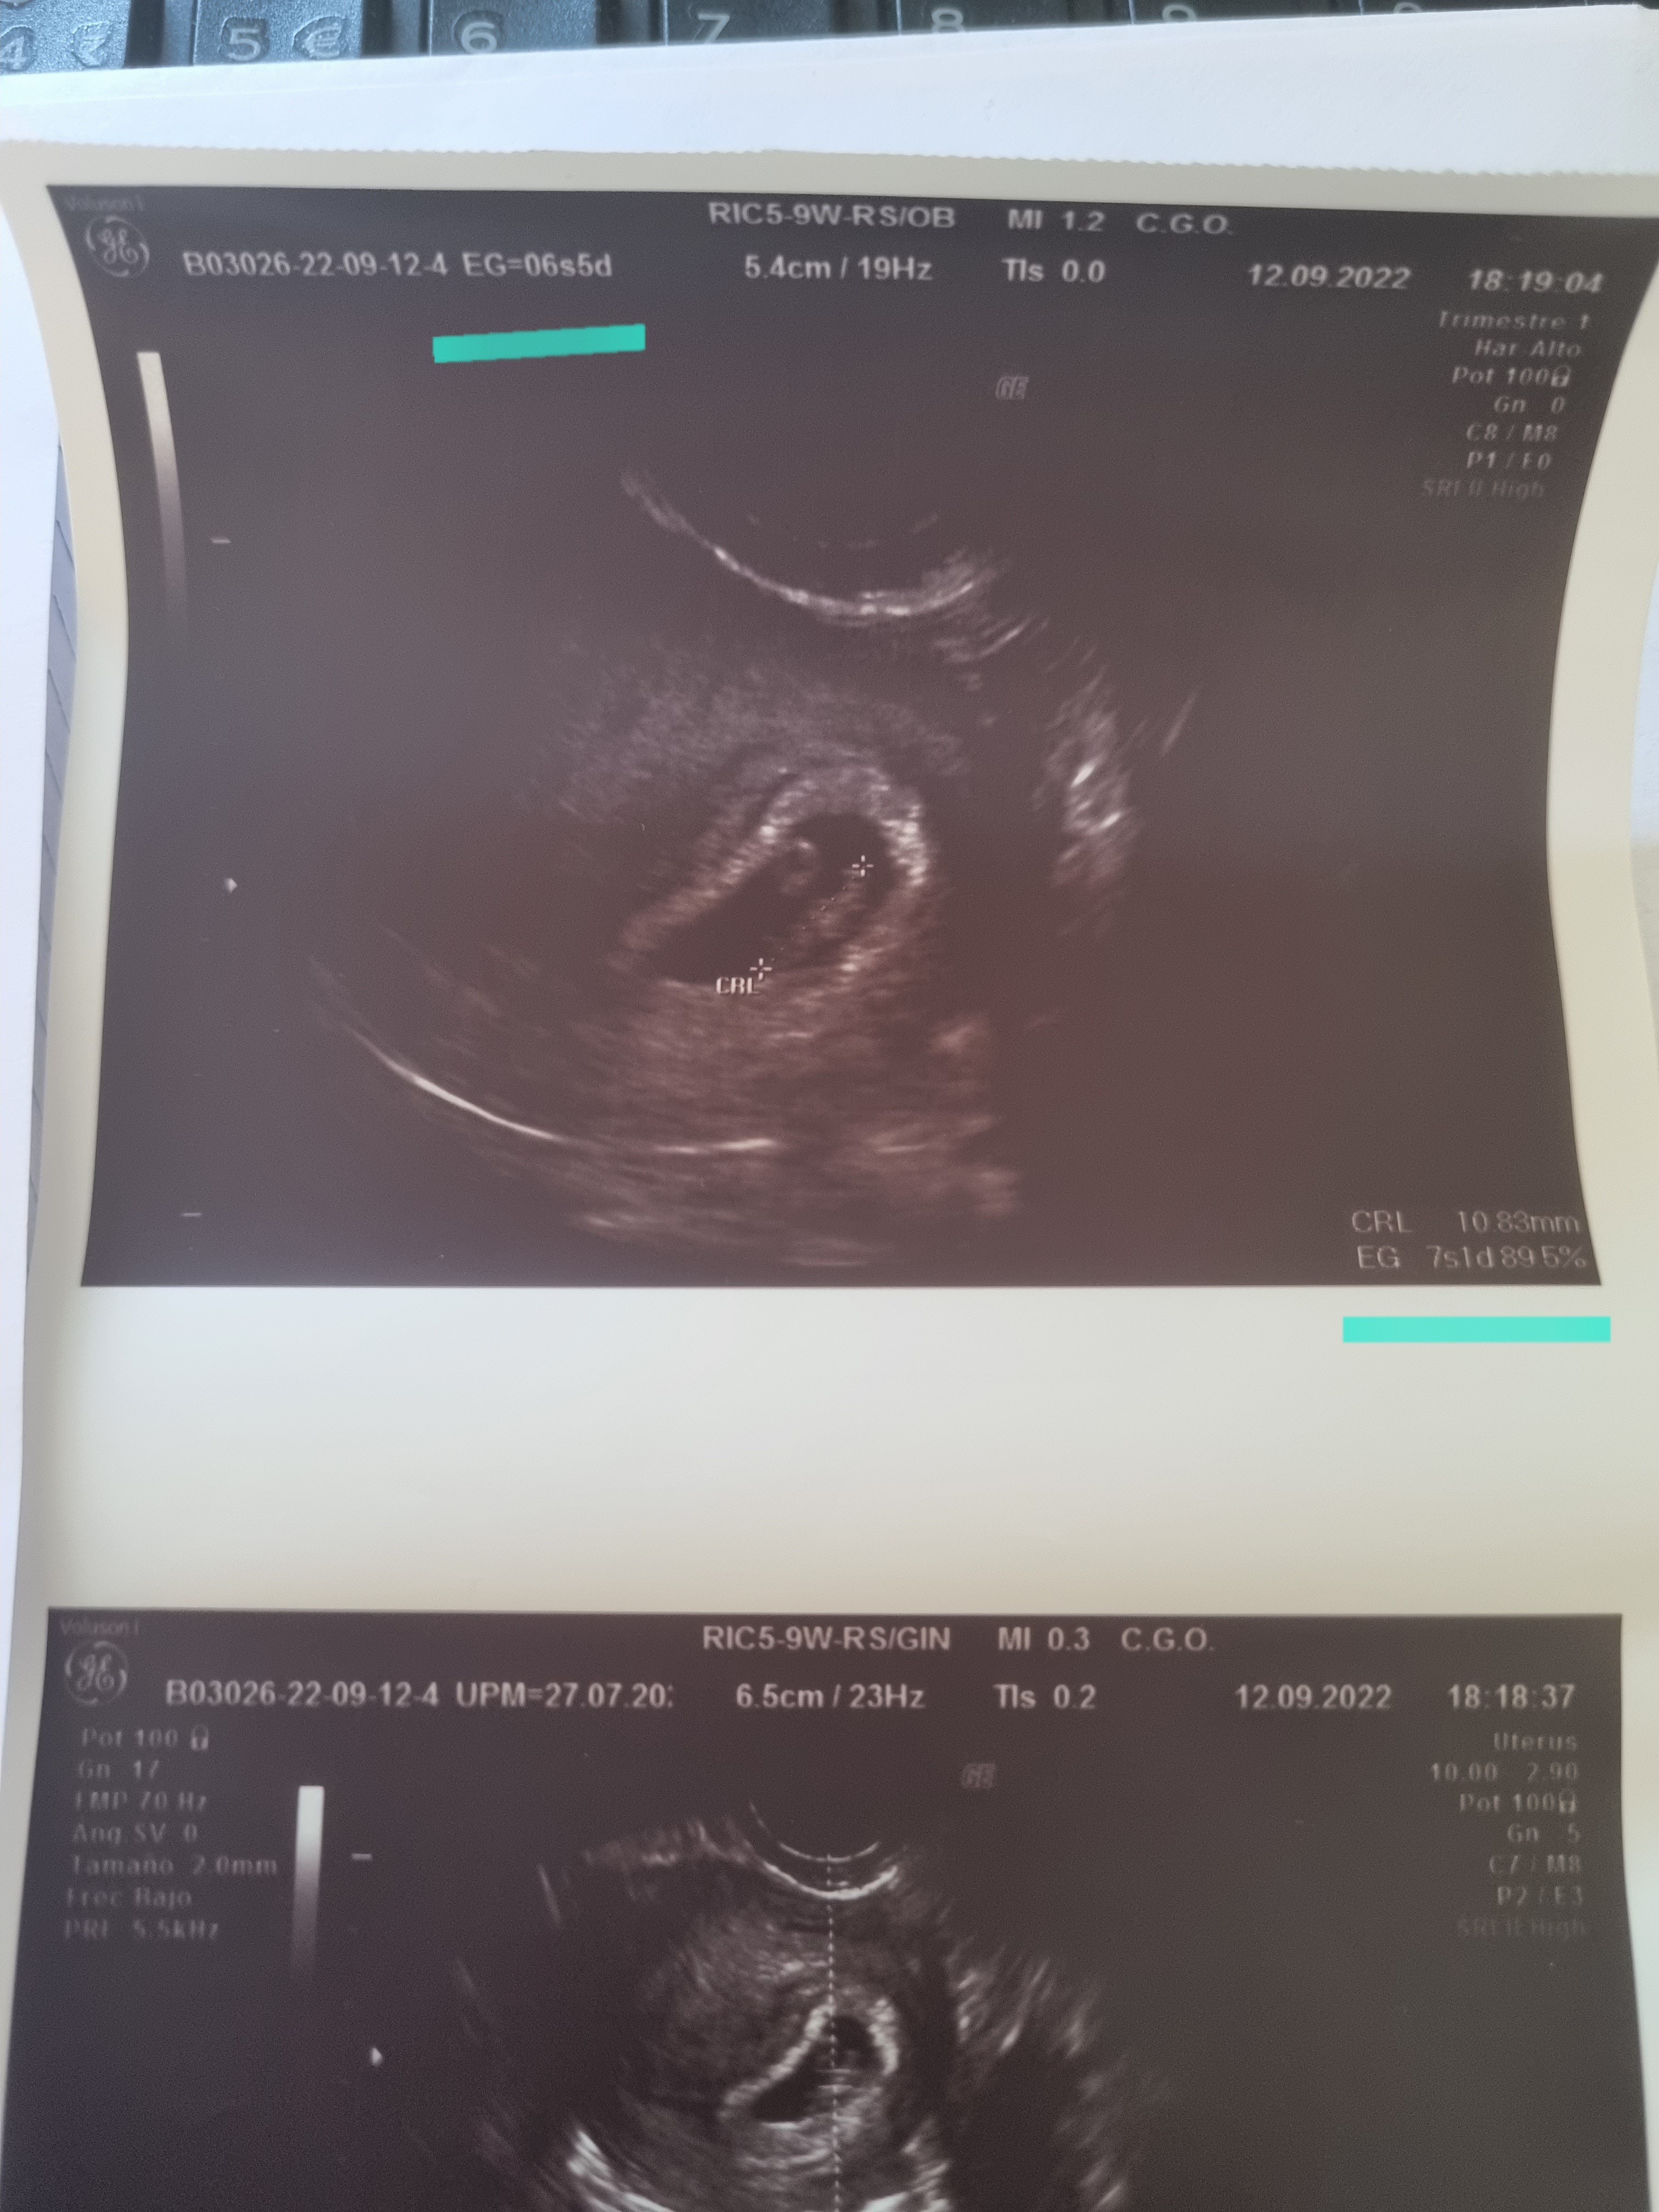

Dziewczyny, dzisiaj robiłam betę i wyszła 5686.07, ostatni raz badałam tydzień temu dokładnie i była 319.62. wiem że powinnam co 48h ale mieszkam na takim zadupiu że pobieranie krwi tylko od 7-11 i tylko od pon-pt a ja wtedy pracuję... (Nie ma u nas żadnej diagnostyki czy czegoś innego i po wynik trzeba sobie dreptać do punktu

Chyba mogę lekko zacząć się cieszyć i przestać martwić